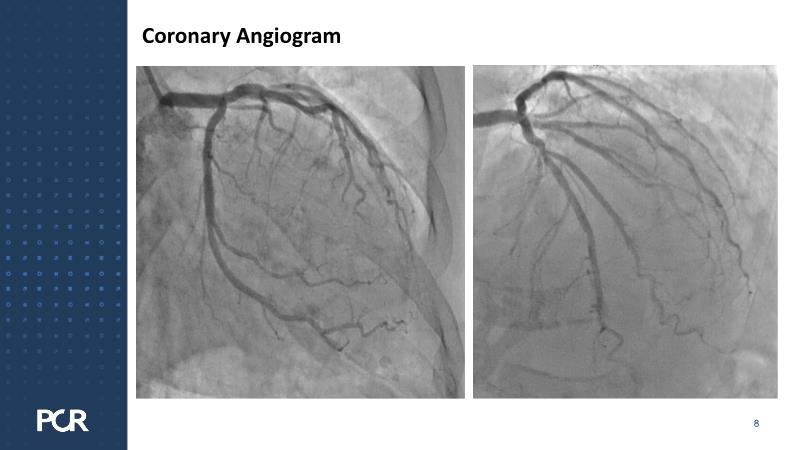

Delve into advanced transcatheter aortic valve implantation (TAVI) with the Evolut FX plus system, focusing on its application in patients with small annulus and coronary artery disease (CAD). This session details step-by-step deployment, patient selection, imaging analysis, and highlights the distinctions from the previous Evolut R platform to improve clinical outcomes.